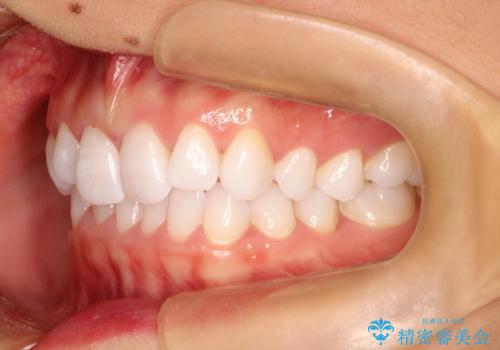

気になる前歯の歯並びをインビザラインで矯正

- 前歯の傾きと、ガタガタが気になるとのことで来院されました。

アスリートの方でしたので、競技に支障が少ないインビザラインで治療することとなりました。

前歯の傾きや高さをシミュレーションで患者様と確認しながら、歯並びを仕上げていきました。